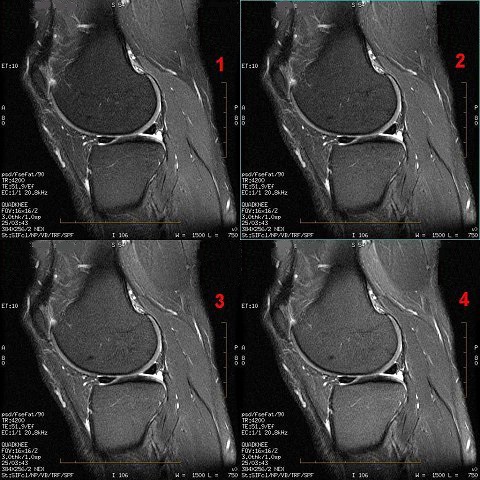

Fat Saturation Efficiency

Use Fat Saturation Efficiency to control the amount of fat that is saturated when either Fat SAT or Classic Fat SAT are selected from the Scan Parameters area. For more information, see Prescribe a chemical SAT pulse.

- The default setting is 0.65 and the range is from 0.5 to 1.0.

- Adjust the Fat Saturation value based on the amount of saturation desired from the fat signal. As the fat saturation value increases, more fat is suppressed:

- Set the value to 0.5 to make fat the brightest possible intensity.

- Set the value to 1.0 to make fat the darkest intensity.